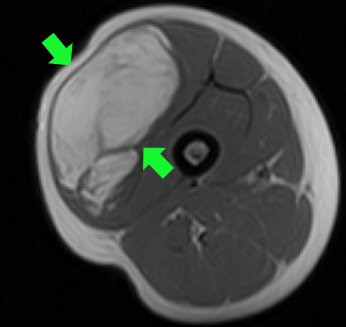

MRI, that is, magnetic resonance imaging, has a very important place in orthopedic oncology. MRI is particularly useful in demonstrating soft tissues. It is the most accepted method in bone tumors with soft tissue components and all kinds of soft tissue tumors. On the other hand, the shots must be done correctly. Otherwise, it is inevitable that the patient will have to undergo MRI several times. This means a waste of time. Especially in malignant bone tumors, MRI is of great importance so that the whole bone can be seen (pic-28). The patient should not be intervened until a sufficient quality MRI is taken. MRI must be taken with intravenous contrast material.